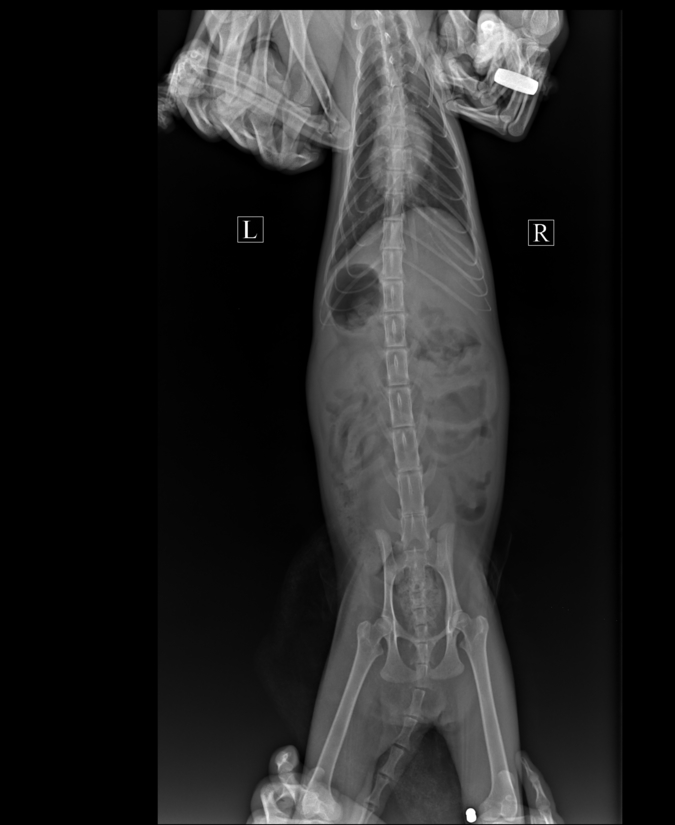

В Еву стреляли из пневматики!!! В лапе пуля. В основании хвоста перелом позвонков. Врач сказал, что операцию сделать можно, но шансы 50/50 что она поможет. Стоимость операции 10-12 тыс. Рекомендации выложу завтра. Пока только фото.

Рентген и заключение врача.

xray_0.preview.thumb.jpg.970123fc75fe01a04c70bb2e59414faf.jpg   xray_1.preview.thumb.jpg.15fcb9ee13e4cca120089914dce6c6e9.jpg   49.thumb.jpg.09da0312eefcdca72cb93c683f4002ae.jpg